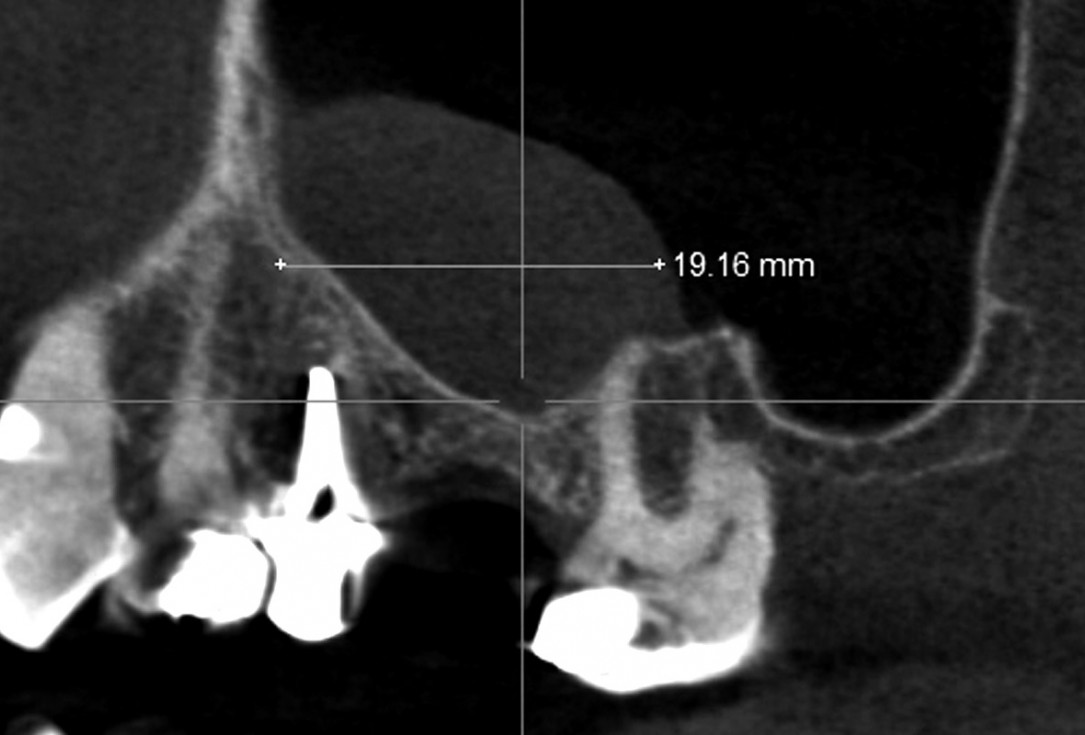

02/35 - CBCT shows maxillary sinus cystMaxillary sinus cyst removal using the Crocodile Technique and subsequent lateral sinus lift - Dres. C. Scognamiglio and A. Perucchi

03/35 - CBCT shows maxillary sinus cystMaxillary sinus cyst removal using the Crocodile Technique and subsequent lateral sinus lift - Dres. C. Scognamiglio and A. Perucchi